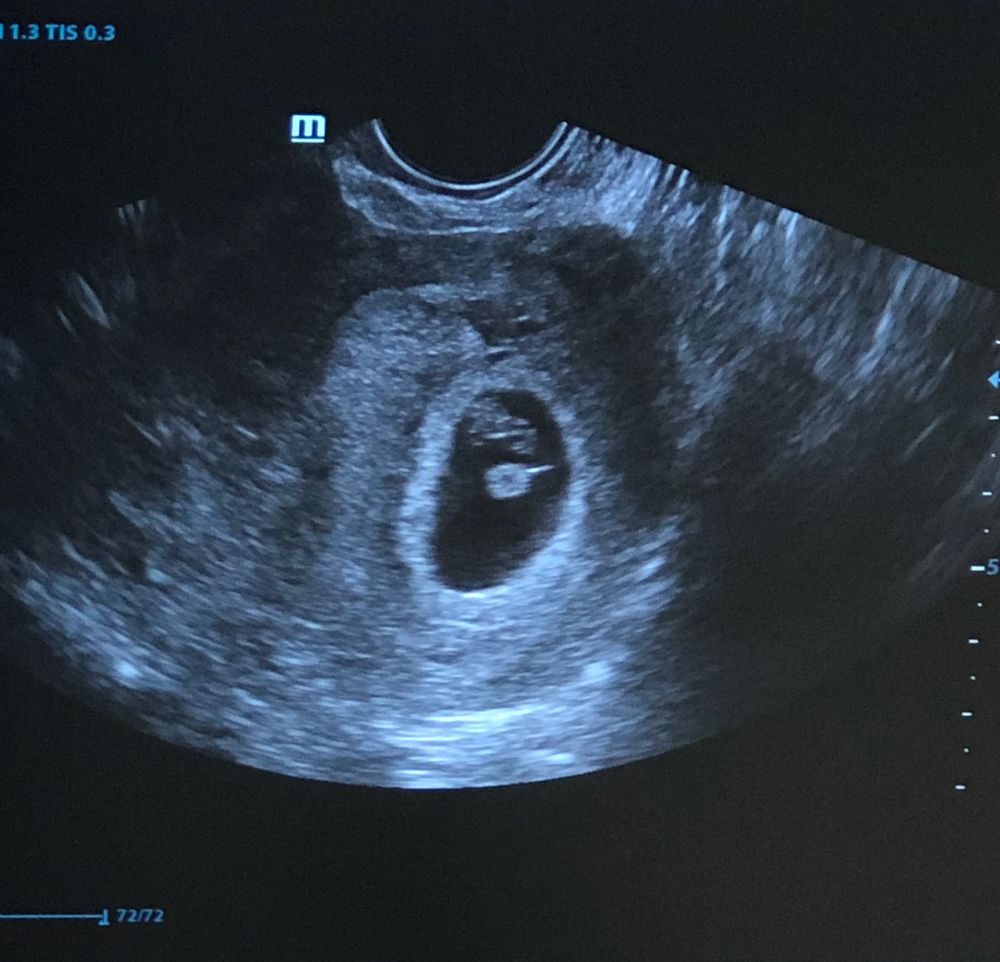

Лариса , вот у меня три снимка с узи))) Изображение Изображение

Екатерина, это с 8-9 недель? Если да, то поздновато для этого метода. Но я бы предположила мальчика, если узи вагинальное. Завтра отпишитесь 🙏☺️

Лариса , да, узи вагинально и примерно это было даже 10 недель..

Лариса , узи вагинально , скажите пожалуйста у меня кто получается по этому методу ? Изображение

bravo gun, у вас справа больше - к девочке.